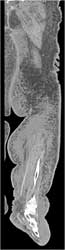

Cellulitis